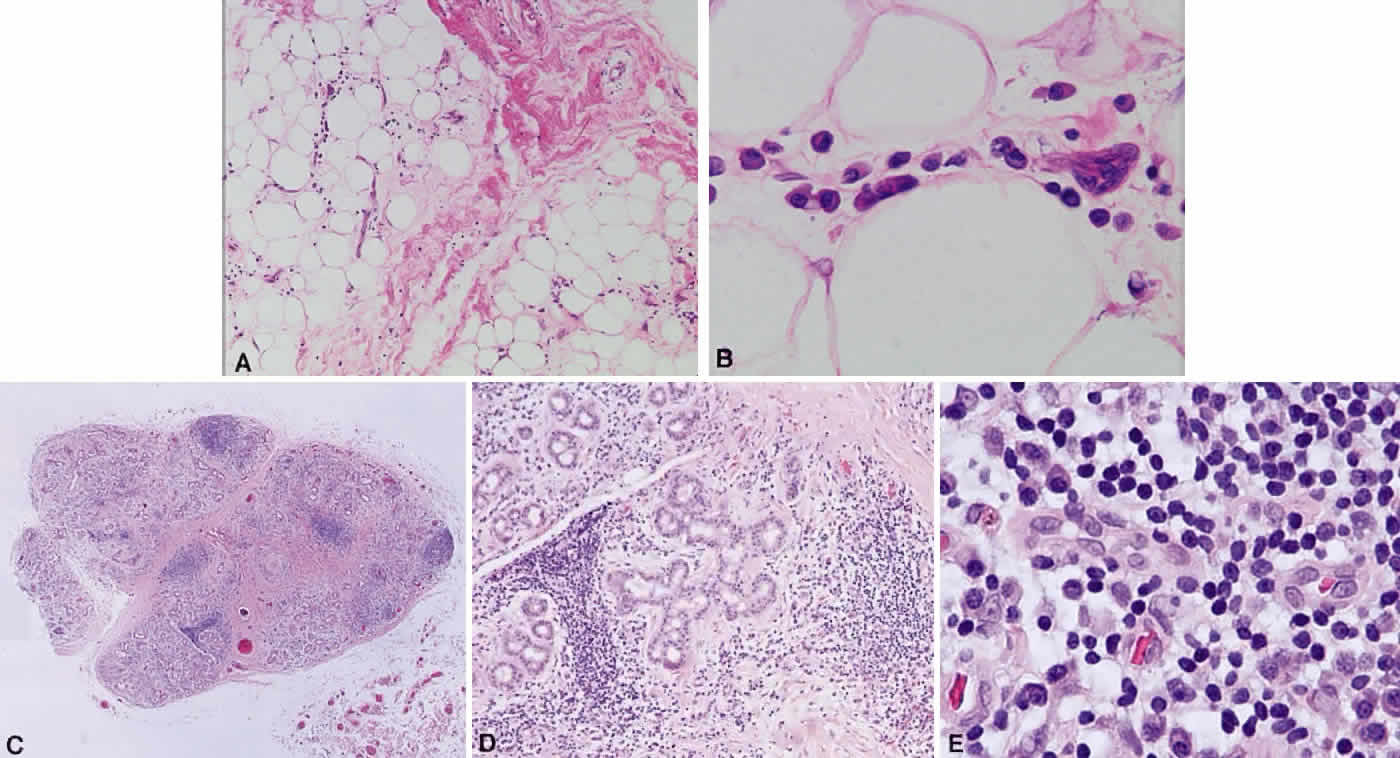

B cells arise from the bone marrow and produce immunoglobulin in a humoral response. T cells are thymus-derived and respond in a cell-mediated reaction via cells that are antigenically marked or produce lymphokines. Circulating blood and lymph nodes normally have a ratio of 70% T cells and 30% B cells, natural killer cells, or null cells. The normal lymph node is composed of follicles, each with germinal centers, mantle zones, and surrounding cortex (Fig. 2). The germinal center is composed of a framework of dendritic histiocytes, follicular dendritic cells, centroblasts, centrocytes, immunoblasts, small lymphocytes, and tingible body macrophages, whereas the surrounding cortex and paracortex consist mainly of B and T cells, respectively. Lymphomatous B cells were initially identified histologically using heterosera against immunoglobulin, which could then be stained with immunoperoxidase stain or rendered fluorescent with immunofluorescent markers.1b Plasma cells could be similarly identified by their cytoplasmic immunoglobulin. T cells were first identified cytologically by their rosette formation when combined with sheep erythrocytes.2 In addition, they were noted to uniquely contain cytoplasmic alphanaphthyl esterase, for which they could be stained histologically.3 Information regarding B-cell clonality could be obtained by staining for immunoglobulin, in particular, kappa and lambda light chains. In benign lesions, the kappa-lambda ratio of B-cell production is 2:1, whereas in malignant lesions, the ratio increases to 10:1.3 Benign and atypical reactive lesions have 50% or greater T cells, whereas malignant B-cell lesions usually consist of only 10% to 20% T cells.3 Malignant T-cell lymphomas, on the other hand, consist of 90% T cells.3 In reactive lesions, the T-cell helper-to-suppressor ratio is increased from the normal 2:1 to 5:1, whereas the normal ratio is maintained in malignant B-cell lymphoma.3 Thus, information about cell lines and immunoglobulin can be used to determine the predominant cell type, the cell type ratio, and the monoclonality or polyclonality of the B-cell population from the immunoglobulin expressed. Reactive processes have been thought to result from polyclonal or oligoclonal populations wherein every distinct clonal population expresses a distinct gene rearrangement, whereas a malignant lymphoma is thought to arise from a monoclonal clone population, which would express only a single gene rearrangement. Polymerase chain reaction has been used to specifically amplify clonal immunoglobulin gene rearrangements. In addition, cell surface markers of the various cell lines have been identified, beginning with the immunoglobulins and interleukins, and, later, cell surface antigen receptors, termed clusters of differentiation (CD), which are used to characterize the degree of differentiation of the cell type in question.4,5 The list of identified cell surface markers subsequently has expanded to over 100 and has aided in the characterization of Hodgkin's lymphoma and different subsets of nonHodgkin's B- and T-cell lymphomas6 (Table 1).

Immunoglobulins have been studied at the molecular level in lymphoma. Monoclonal lymphoid lesions express gene rearrangements that can be detected with restriction endonuclease cleavage and Southern blot.13–25 The gene rearrangement appears as a unique band on the blot, known as a DNA fingerprint, and a polyclonal lesion, which expresses the immunoglobulins made by several different lymphocyte populations in undetectable amounts, then would demonstrate only the control band (Fig. 3). Many cytogenetic abnormalities that are characteristic of certain lymphoma subtypes have been isolated, mostly in the form of chromosomal translocations, some of which have been recognized to cause upregulation of protooncogenes, upregulation of transcription factors, and downregulation of factors involved in apoptosis. Chromosomal translocations are thought to occur so frequently in lymphoma because they take place during the normal process of B-cell differentiation. Examples of mutations and the affected gene include the c-myc oncogene (8q24) in Burkitt's Lymphoma, the bcl-1 gene (11q13) in mantle cell lymphoma, the bcl-2 (18q21) in follicular lymphoma, the bcl-2 t(14;18) gene in 70% to 90% of follicular lymphomas and 10% to 35% of nodal large cell lymphomas, the bcl-6 gene (3q27) in diffuse large cell lymphoma, and the PAX-5 gene t(9;14)(p13;q32) identified in 50% of lymphoplasmacytoid lymphomas25–37 (Table 2). The genes that are overexpressed or underexpressed, as a result of the mutations or translocations, have begun to be elucidated. The bcl-2 gene is a regulator of normal cell apoptosis.34 The t(14:18) translocation of bcl-2 is thought to allow unregulated cell longevity of the centrocytes in follicular lymphoma. The c-myc gene is known to code for a protooncogene, which, when upregulated, allows for unmitigated cell division.26,27 The PAX-5 gene belongs to a family of PAX genes, which have been identified as critical regulators of the cell cycle and differentiation.27,31,35 In particular, PAX-5 (BSAP) codes for the B-cell-specific transcription factor expressed in all stages of B-cell differentiation except in plasma cells.35 BSAP factor is suspected of enhancing B-cell lymphopoiesis, but the exact mechanism is not known. A mutation in bcl-1 allows for upregulation of the PRAD-1 gene, which codes for cyclin D1, a cell cycle regulator.26,27

While the Lukes-Collins and Working Formulation classifications were in wide use in the United States, the European literature made references to the Kiel and updated Kiel classifications, which led to disparities in classifying lymphoma. Another classification proposed by Jakobiec and coworkers was the most comprehensive classification available for orbital disease but failed to integrate systemic lymphoma, which is known to be associated in approximately half of cases.1 The most recent classification has made the system universal, comprehensive, and useful to interdisciplinary teams that characteristically manage patients with lymphoma. The International Lymphoma Study Group in 1994 developed the Revised European-American Lymphoma (REAL) classification (Table 5), which classifies lymphoid disease by the cell of origin into B-cell, T-cell, and natural killer cell lymphomas, leukemias, myeloma, and variants of Hodgkin's disease26 (Fig. 4). The identification of the putative benign progenitor cells has been inferred through the use of cell marker studies. The results of molecular genetic studies to identify immunoglobulin gene rearrangements and cytogenetic studies to detect chromosomal translocations in monoclonal proliferations have also been incorporated. A significant contribution of the REAL classification has been to incorporate primary extranodal lymphomas as recognizable and classifiable entities. As a result, new variants in this list include lymphoplasmacytic lymphoma, mantle cell lymphoma, marginal zone B-cell lymphoma, particularly mucosal-associated lymphoid tissue (MALT) lymphoma, subclasses of large cell lymphoma, and the natural killer cell lymphomas. Comparisons of the REAL classification to the Working Formulation and the Kiel classification are shown in Tables 6 and 7, respectively.48 The first series of 112 orbital lymphomas using the REAL classification reported the accuracy and utility of the system in classifying orbital lesions and predicting prognosis in combination with currently available immunophenotyping and immunocytogenetic studies.49 The REAL classification does not classify disease based on the degree of differentiation or clinical prognosis. However, a proposed prognostic scheme has been developed in accordance with the REAL classification28 (Table 8). In this text, tumor nomenclature adheres as strictly as possible to the REAL classification.